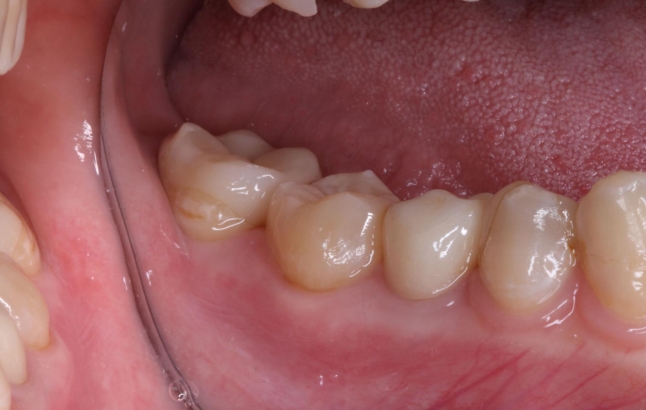

歯牙移植による右下部位の治療例

- 年代、性別 20代・女性

- 来院動機 他院で右下の歯を抜き、インプラントを勧められたが、歯牙移植ができないか相談したいと来院されました。

- 治療内容 右下の残せない歯を抜歯し、ご自身の不要な親知らずを取り出して、右下の抜歯部に移植しました。

- 治療期間 約2週間

- 治療費用 176,000円(税込)

以下の写真の患者様は、移植した歯の歯根根の成長がまだ終わっていなかったため、歯を削ったり神経を取ったりすることなく、移植から11年経った現在も、そのままの状態で自分の歯として元気に機能しています。